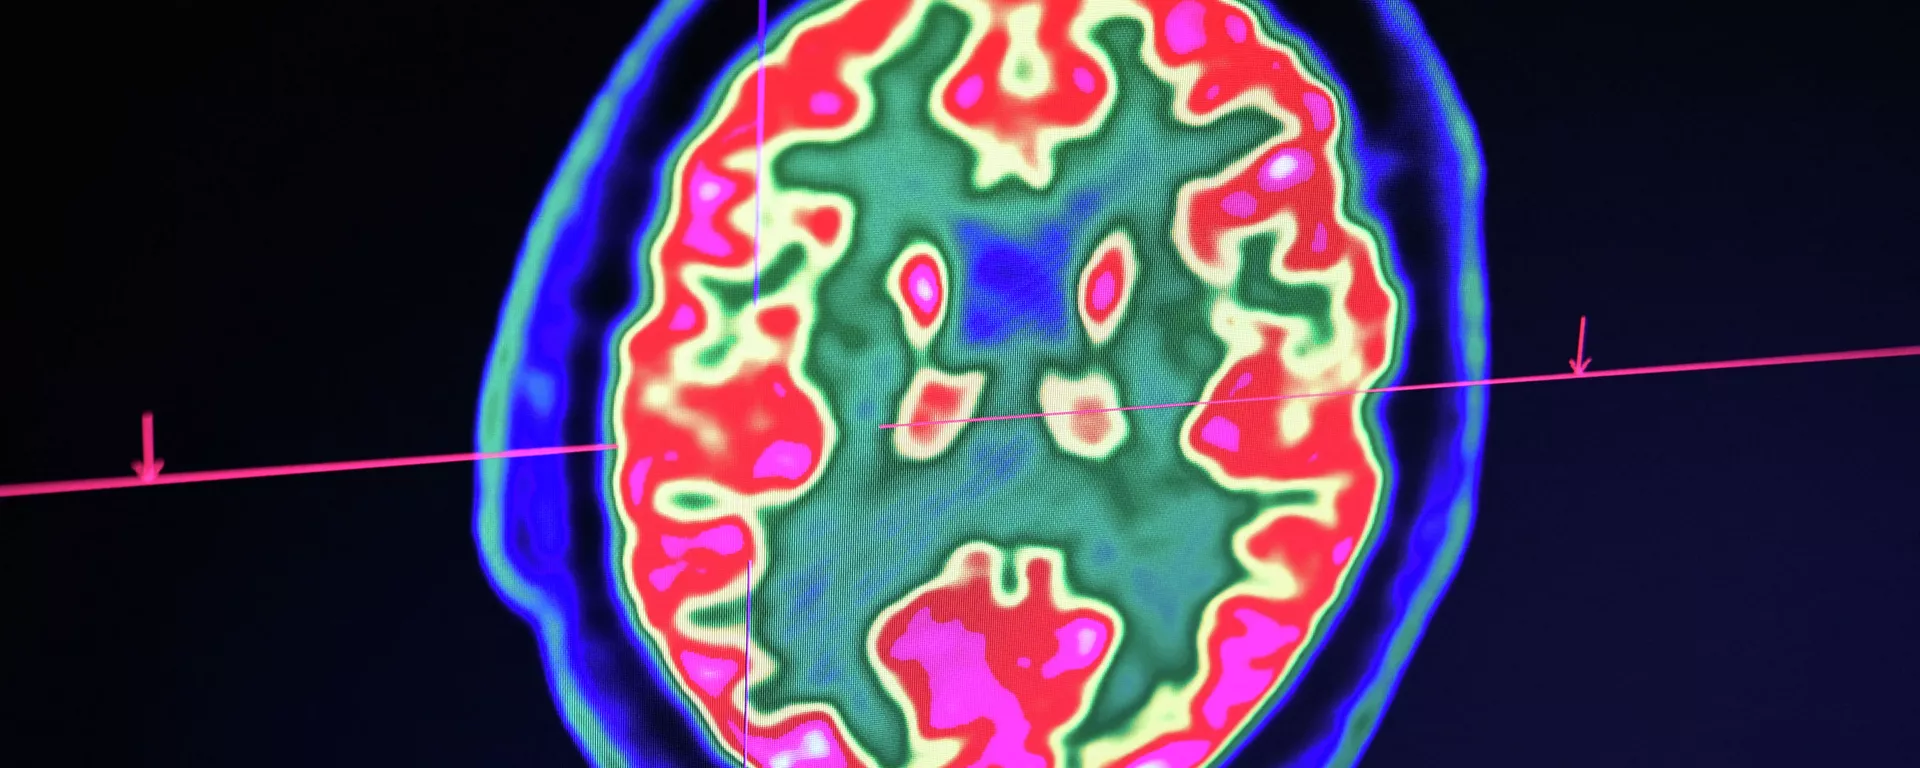

Основные причины потери памяти назвали ученые

БИШКЕК, 29 окт — Sputnik. Основные причины потери памяти назвали ученые Национального института по проблемам старения в США, пишет портал Eat This! Not That!.

По их данным, к потере памяти приводят старение, плохой сон, депрессия, ненормальная реакция на лекарства, употребление алкоголя, травма головы, нехватка витамина В12.

"С возрастом изменения происходят во всех частях тела, в том числе в мозге. В результате некоторые люди могут заметить, что на изучение нового уходит больше времени, они уже не запоминают информацию хорошо", — рассказали ученые.

Они напомнили, что потеря памяти — не всегда признак слабоумия. О деменции — серьезном прогрессивном заболевании мозга — могут говорить несколько симптомов. Это проблемы с запоминанием недавно полученной информации или событий, сложности в общении, например, проблемы с поиском нужных слов. Такой человек может заблудиться в знакомой местности, часто путает рецепты, ошибается во времени и забывает людей.